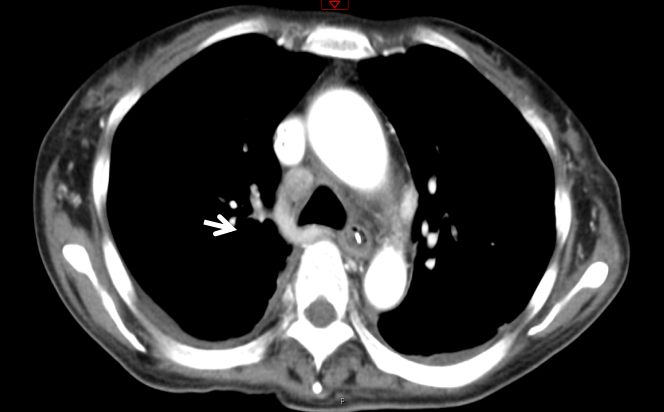

入室诊断:发热查因:结节病?腹膜炎,肺部感染。处理措施包括应用抗生素前行病原学检查;暂予泰能及替考拉宁抗感染,并加强支持治疗。但病情改善不明显。入院第4天(2020-01-21)收到血及腹水培养结果:马尔尼菲篮状菌。修正诊断:马尔尼菲篮状菌感染;肺部感染;腹腔感染;肝功能损伤;胸腔积液;腹腔积液。立即给予两性霉素B治疗。首剂15 mg, 每日增加5 mg, 第4日30 mg, 同时患者热退,胸腹腔积液减少,肝功能好转,凝血功能紊乱纠正,PLT稳步提高。2020-01-31转到呼吸科进一步治疗,两性霉素B疗程满2周,累计量480 mg后序贯伊曲康唑口服治疗,治疗12 d后纵膈淋巴结缩小,患者痊愈出院,出院前CT检查见图 4,WBC等指标变化见图 5。

| 图 4 出院前2020-02-03 CT检查影像示纵膈变化 |